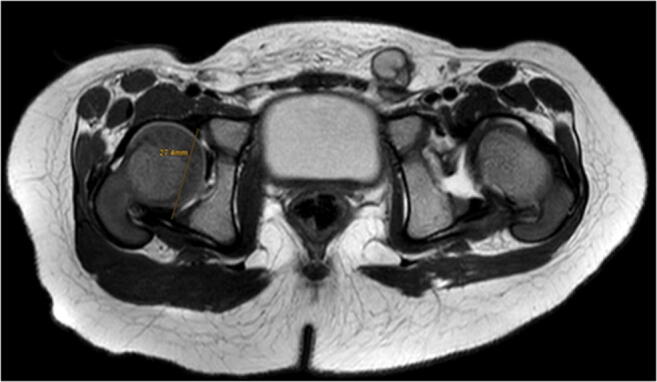

For MRI, patients were placed in supine position with the previously applied pelvic cast. In most cases, images were obtained without additional anaesthesia using a Philips Ingenia System (Philips Healthcare, Best, The Netherlands) at field strengths of either 1.5 Tesla (T) or 3.0 T. T2-weighted turbo spin echo (TSE) sequences in the transverse and coronal plane were used to evaluate the correct reposition of the hip. The slice thickness was set to 2.5 mm. For measuring femoral head volumes (Fig. 1) and acetabular diameters (Fig. 2), IntelliSpace Portal (Version 10.1, Philips Medical Systems, Best, Netherlands) was used. For volumetry, the femoral head was segmented in each axial slice. The largest acetabular diameter was also measured in axial sequences. Acetabular opening area was calculated by Ao = πd2/4. All measurements were performed by three radiologists with routine in MR imaging for both DDH and contralateral, healthy hips. For estimation of intra-observer reliability, measurement was repeated six months after the initial measurement.

Fig. 1.

a A coronal projection of a DDH of the right side and b its corresponding transversal projection after successful closed reduction. c The principle of measurement for femoral head’s volume at one level